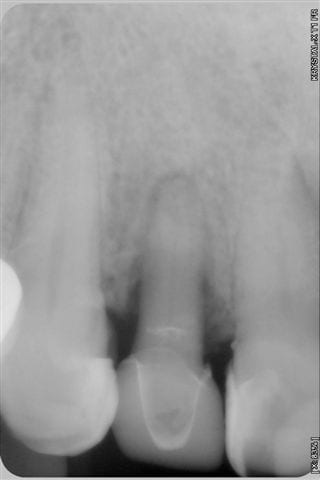

Souvenez vous, il y a 6 mois, je vous ai posté des photos sur un cas de parodontopathie aiguë localisée à la 12, voici les photos et radio 6 mois plus tard, après traitement de la paro au laser diode 980 nm sous bipivone puis H2O2, bio stimulation tous les 15 jours et reconstruction de la couronne en emax avec le CEREC 6 mois plus tard.

Résultat clinique et radiologique plutôt encourageant à 6 mois.

- Voici 1 cas apparemment réussi à 6 mois. Le Cerec n'a rien à voir dans l'affaire, c'est juste un moyen comme un autre de faire une restauration coronaire. Le problème est celui du traitement parodontal par laser.